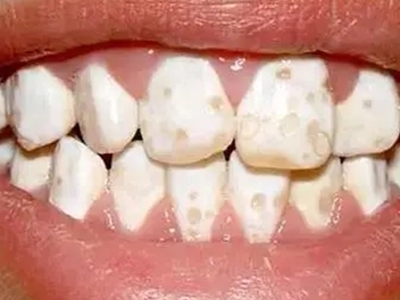

牙齿

牙釉质发育不全牙齿布满白斑图

牙釉质发育不全患者的牙齿形态完整,釉质呈白垩色改变,表现为牙齿表面布满白色的斑块,导致牙齿的通透性明显降低,牙齿功能正常,有美观需求的患者可使用瓷贴面、烤瓷冠等方法进行修复治疗。